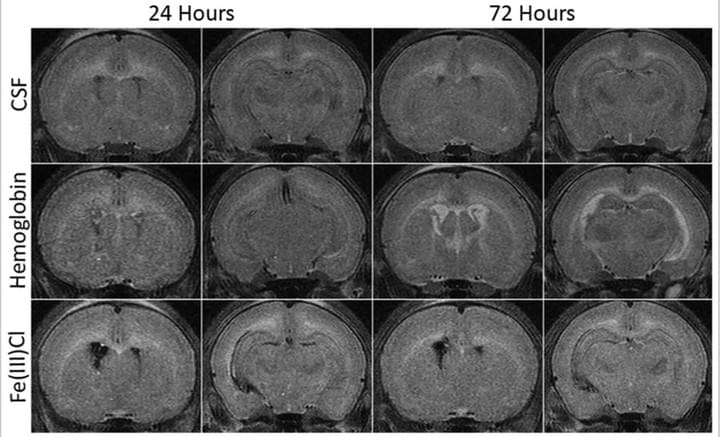

Role of red blood cell lysis and iron in hydrocephalus after intraventricular hemorrhage

J Cereb Blood Flow Metab. 2014 Jun;34(6):1070-5

In this study investigated the role of red blood cell (RBC) lysis and iron in hydrocephalus after IVH. We found that intraventricular injection of lysed RBCs, but not packed RBCs, resulted in ventricular enlargement and marked increases in brain hemeoxygenase-1 and ferritin at 24 hours. Intraventricular injection of iron also resulted in ventricular enlargement and ventricular wall damage 24 hours later. Coinjection of deferoxamine reduced lysed RBC-induced ventricular enlargement. These results suggest that iron, a degradation product of hemoglobin, has an important role in hydrocephalus development after IVH.

Access full-length article here: https://www.ncbi.nlm.nih.gov/pubmed/24667910